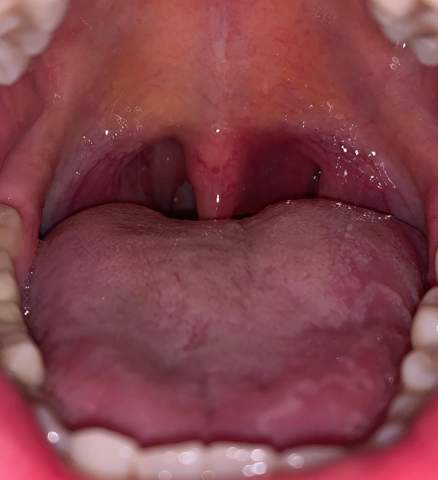

was ist der geschwollene bereich neben dem gaumenzapfchen gesundheit und medizin